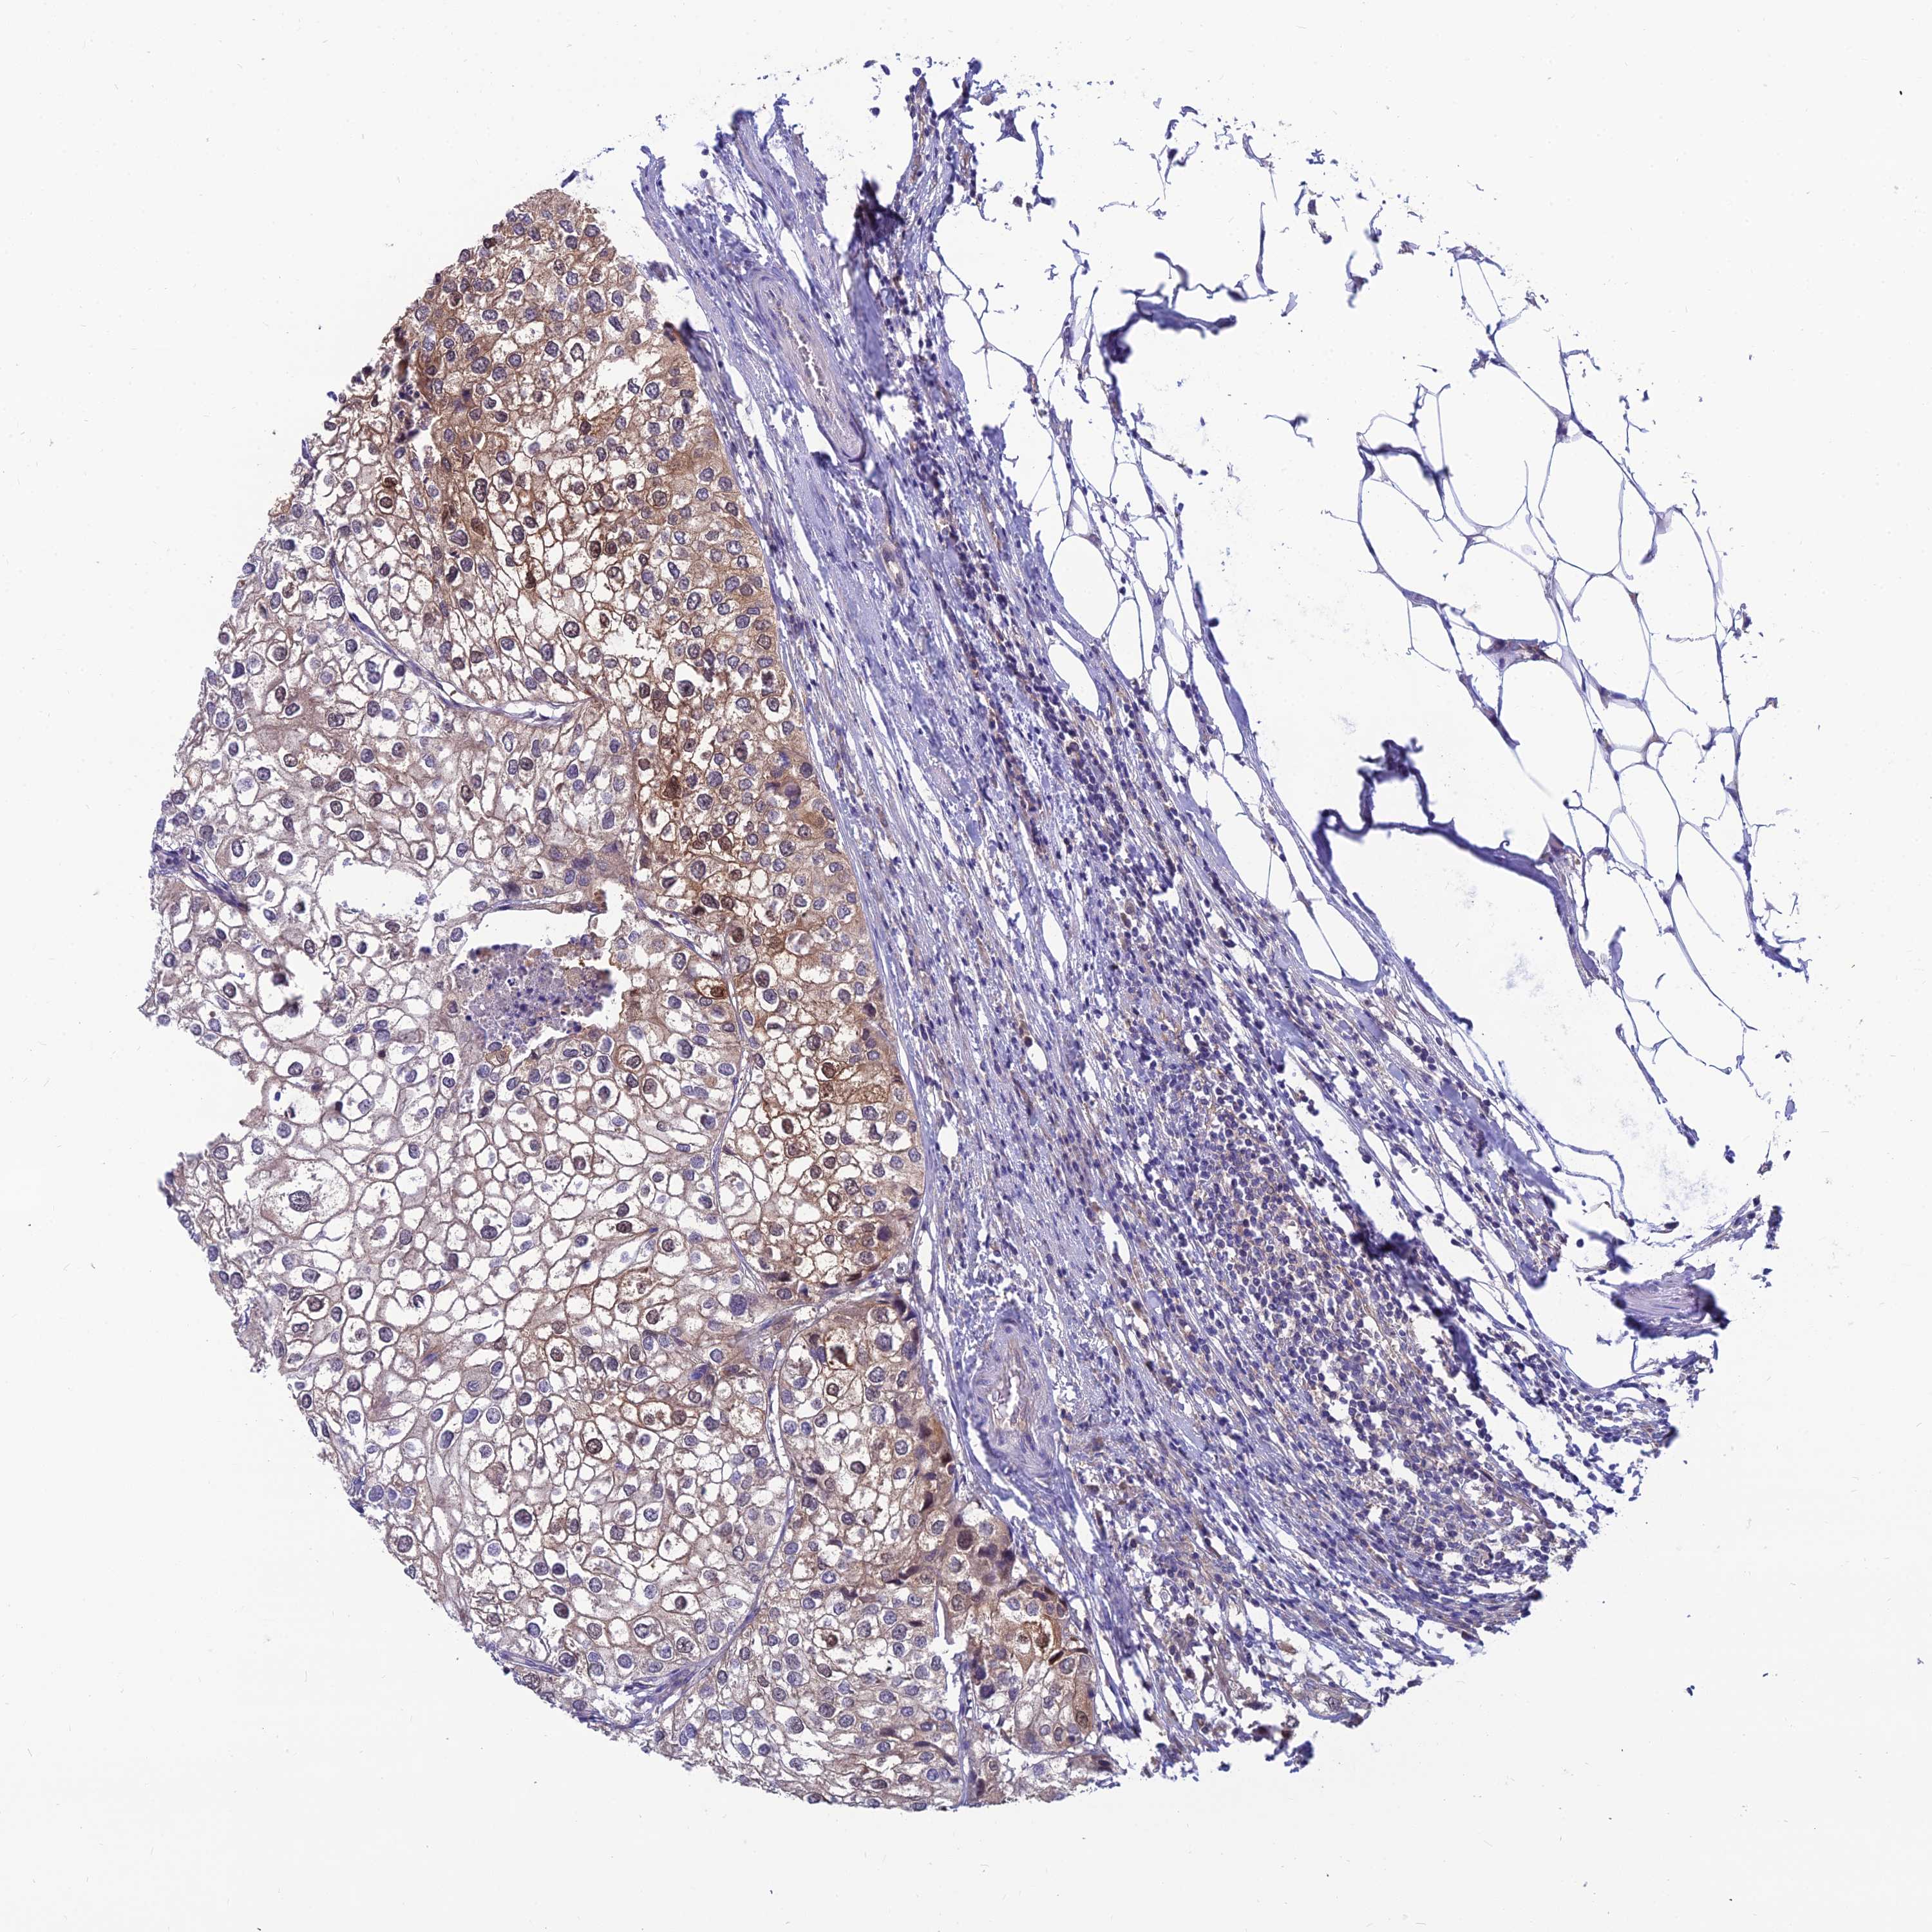

UROTHELIAL CANCER - Protein expressioni

A mouse-over function shows sample information and annotation data. Click on an image to view it in a full screen mode. Samples can be filtered based on level of antibody staining by selecting one or several of the following categories: high, medium, low and not detected. The assay and annotation is described here.

Note that samples used for immunohistochemistry by the Human Protein Atlas do not correspond to samples in the TCGA dataset.

Antibody stainingi

Antibody staining in the annotated cell types in the current human tissue is reported as not detected, low, medium, or high, based on conventional immunohistochemistry profiling in selected tissues. This score is based on the combination of the staining intensity and fraction of stained cells.

Each image is clickable and will lead to virtual microscopy that enables deeper exploration of all samples and also displays staining intensity scores, fraction scores and subcellular localization as well as patient and tissue information for each sample.

Antibody HPA041404

Antibody HPA048250

Staining

High

Medium

Low

Not detected

Intensity

Strong

Moderate

Weak

Negative

Quantity

>75%

75%-25%

<25%

None

Location

Nuclear

Cytoplasmic/membranous

Cytoplasmic/membranous,nuclear

Urothelial carcinoma, High grade

Urothelial carcinoma, Low grade